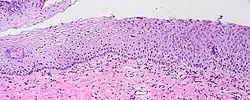

Squamous intraepithelial lesion

A squamous intraepithelial lesion (SIL) is an abnormal growth of squamous cells on the surface of the cervix; normal squamous cells make up the normal epithelium of the cervix. This lesion can progress to cervical cancer and can be diagnosed using a Pap smear or a colposcopy. It can be treated by using methods that remove the abnormal cells, allowing normal cells to grow in their place.[1] In the Bethesda system, the cytology can be graded as LSIL (low-grade squamous intraepithelial lesion) or HSIL (high-grade squamous intraepithelial lesion).